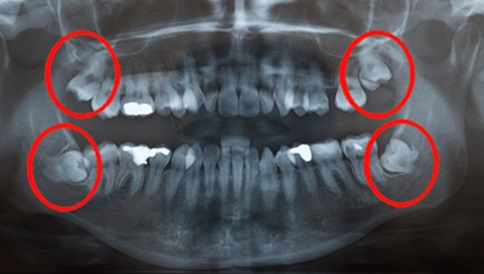

The most common impactions are seen in cases of wisdom teeth (third molars). Sometimes, even canines or other teeth might be found impacted in one's mouth.

If the impaction is between the third molar and part of the second molar, this kind is called bone impaction. It can sub categorized into vertical, horizontal, and angular depending on the way they are intersecting. If the wisdom tooth is directly breaking out of the tissue, it is known as tissue impaction.

The following four impactions are commonly found in patients :

Bone Impaction (Vertical) :Impaction would cause pathosis inside the cheek bone or jaw bone.

Bone Impaction (Horizontal) :Besides leading pathosis, horizontal placement would hurt the hard tissue of the second molar to cause toothache and cavities.

Bone Impaction (Angular) :Besides leading pathosis, angular placement would hurt the hard tissue of the second molar to cause toothache and cavities.

Tissue Impaction :The wisdom tooth almost erupts out of gum, or its half erupts out of gum to cause pseudo-pocket. Besides leading pathosis, it easily tracts food debris and causes gum irritation.